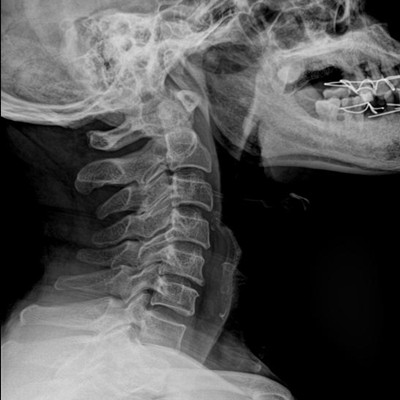

高品質影像鏈 讓您看的更清晰 PLX8500C/D

●大尺寸非晶硅平板探測器。

●非晶硅平板探測器,采用先進的制造工藝、性能更穩(wěn)定。

●探測器可以大范圍轉動,大尺寸有效探測面積,可滿足人體多部位攝影需求。